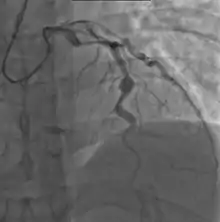

Heart complications are the most important aspect of Kawasaki disease, which is the leading cause of heart disease acquired in childhood in the United States and Japan.[30] In developed nations, it appears to have replaced acute rheumatic fever as the most common cause of acquired heart disease in children.[14] Coronary artery aneurysms occur as a sequela of the vasculitis in 20–25% of untreated children.[51] It is first detected at a mean of 10 days of illness and the peak frequency of coronary artery dilation or aneurysms occurs within four weeks of onset.[47] Aneurysms are classified into small (internal diameter of vessel wall <5 mm), medium (diameter ranging from 5–8 mm), and giant (diameter > 8 mm).[30] Saccular and fusiform aneurysms usually develop between 18 and 25 days after the onset of illness.[14]

Even when treated with high-dose IVIG regimens within the first 10 days of illness, 5% of children with Kawasaki disease develop at the least transient coronary artery dilation and 1% develop giant aneurysms.[52][53][54] Death can occur either due to myocardial infarction secondary to blood clot formation in a coronary artery aneurysm or to rupture of a large coronary artery aneurysm. Death is most common two to 12 weeks after the onset of illness.[14]

Many risk factors predicting coronary artery aneurysms have been identified,[20] including persistent fever after IVIG therapy,[55][56] low hemoglobin concentrations, low albumin concentrations, high white-blood-cell count, high band count, high CRP concentrations, male sex, and age less than one year.[57] Coronary artery lesions resulting from Kawasaki disease change dynamically with time.[3] Resolution one to two years after the onset of the disease has been observed in half of vessels with coronary aneurysms.[58][59] Narrowing of the coronary artery, which occurs as a result of the healing process of the vessel wall, often leads to significant obstruction of the blood vessel and the heart not receiving enough blood and oxygen.[58] This can eventually lead to heart muscle tissue death, i.e., myocardial infarction (MI).[58]

MI caused by thrombotic occlusion in an aneurysmal, stenotic, or both aneurysmal and stenotic coronary artery is the main cause of death from Kawasaki disease.[60] The highest risk of MI occurs in the first year after the onset of the disease.[60] MI in children presents with different symptoms from those in adults. The main symptoms were shock, unrest, vomiting, and abdominal pain; chest pain was most common in older children.[60] Most of these children had the attack occurring during sleep or at rest, and around one-third of attacks were asymptomatic.[14]

- Angiography was historically used to detect coronary artery aneurysms, and remains the gold standard for their detection, but is rarely used today unless coronary artery aneurysms have already been detected by echocardiography.